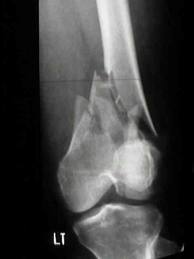

I spent six months in hospital. They let me dictate my exams to someone in a small room, and I was given extra time. The doctor who never once really looked me in the face told me that I would probably never walk again. Well, I wasn't having any of that from him. I insisted on Physio and after two knee replacements and four metal splints in my legs I not only walk but I ride a motorcycle. I wasn't have anyone tell me that I had to stop walking! The police never found the guy that hit me, but they have put a crossing on the road. I was hit at around 40mph, and from the lack of skid marks on the road, the man didn't make any attempt to stop.